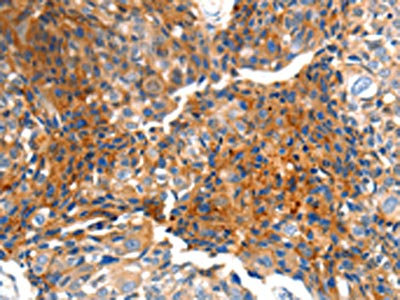

The image on the left is immunohistochemistry of paraffin-embedded Human breast cancer tissue using CSB-PA780156(MTNR1A Antibody) at dilution 1/100, on the right is treated with synthetic peptide. (Original magnification: ×200)